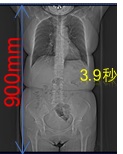

シーメンス社のテクノロジーにより、全身領域において高速スパイラルスキャンが可能です。

高速で230mm/秒で撮影することができ、例としておなか60cmの範囲を撮影するとした場合、約3秒の息止めで撮影することが可能です(検査の種類、目的により異なります)。